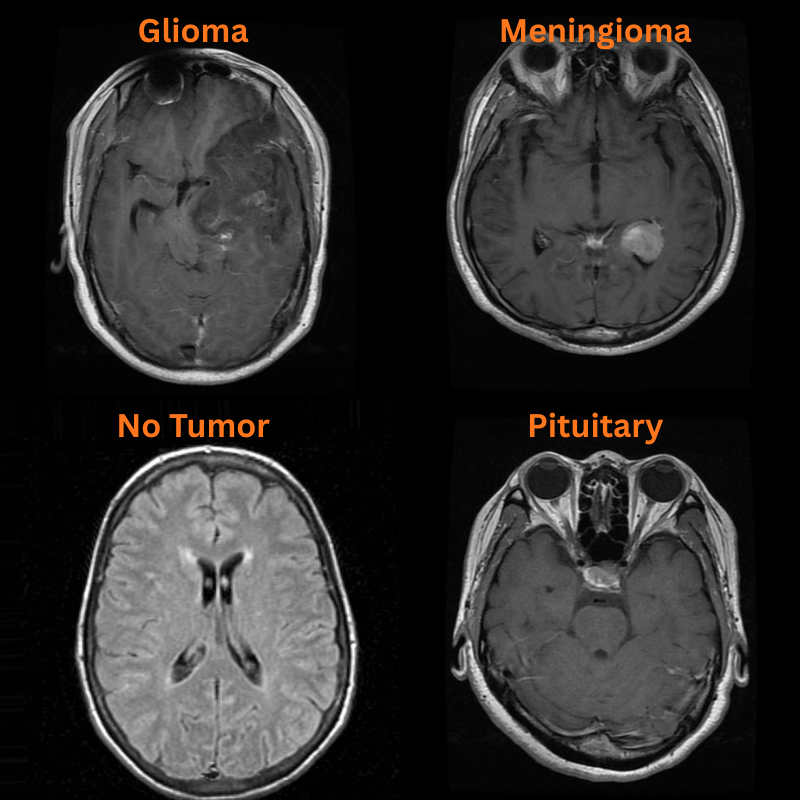

There are two subdirectories, and we will focus on the classification_task one. As we can see, the dataset contains four classes: Glioma, Meningioma, Pituitary Tumor, and No Tumor.

Following are some of the samples from the dataset.

The following are the results. The red text represents the predictions and the green text the ground truth labels.

Apart from one image, that is meningioma predicted as no_tumor, the other three predictions are correct.